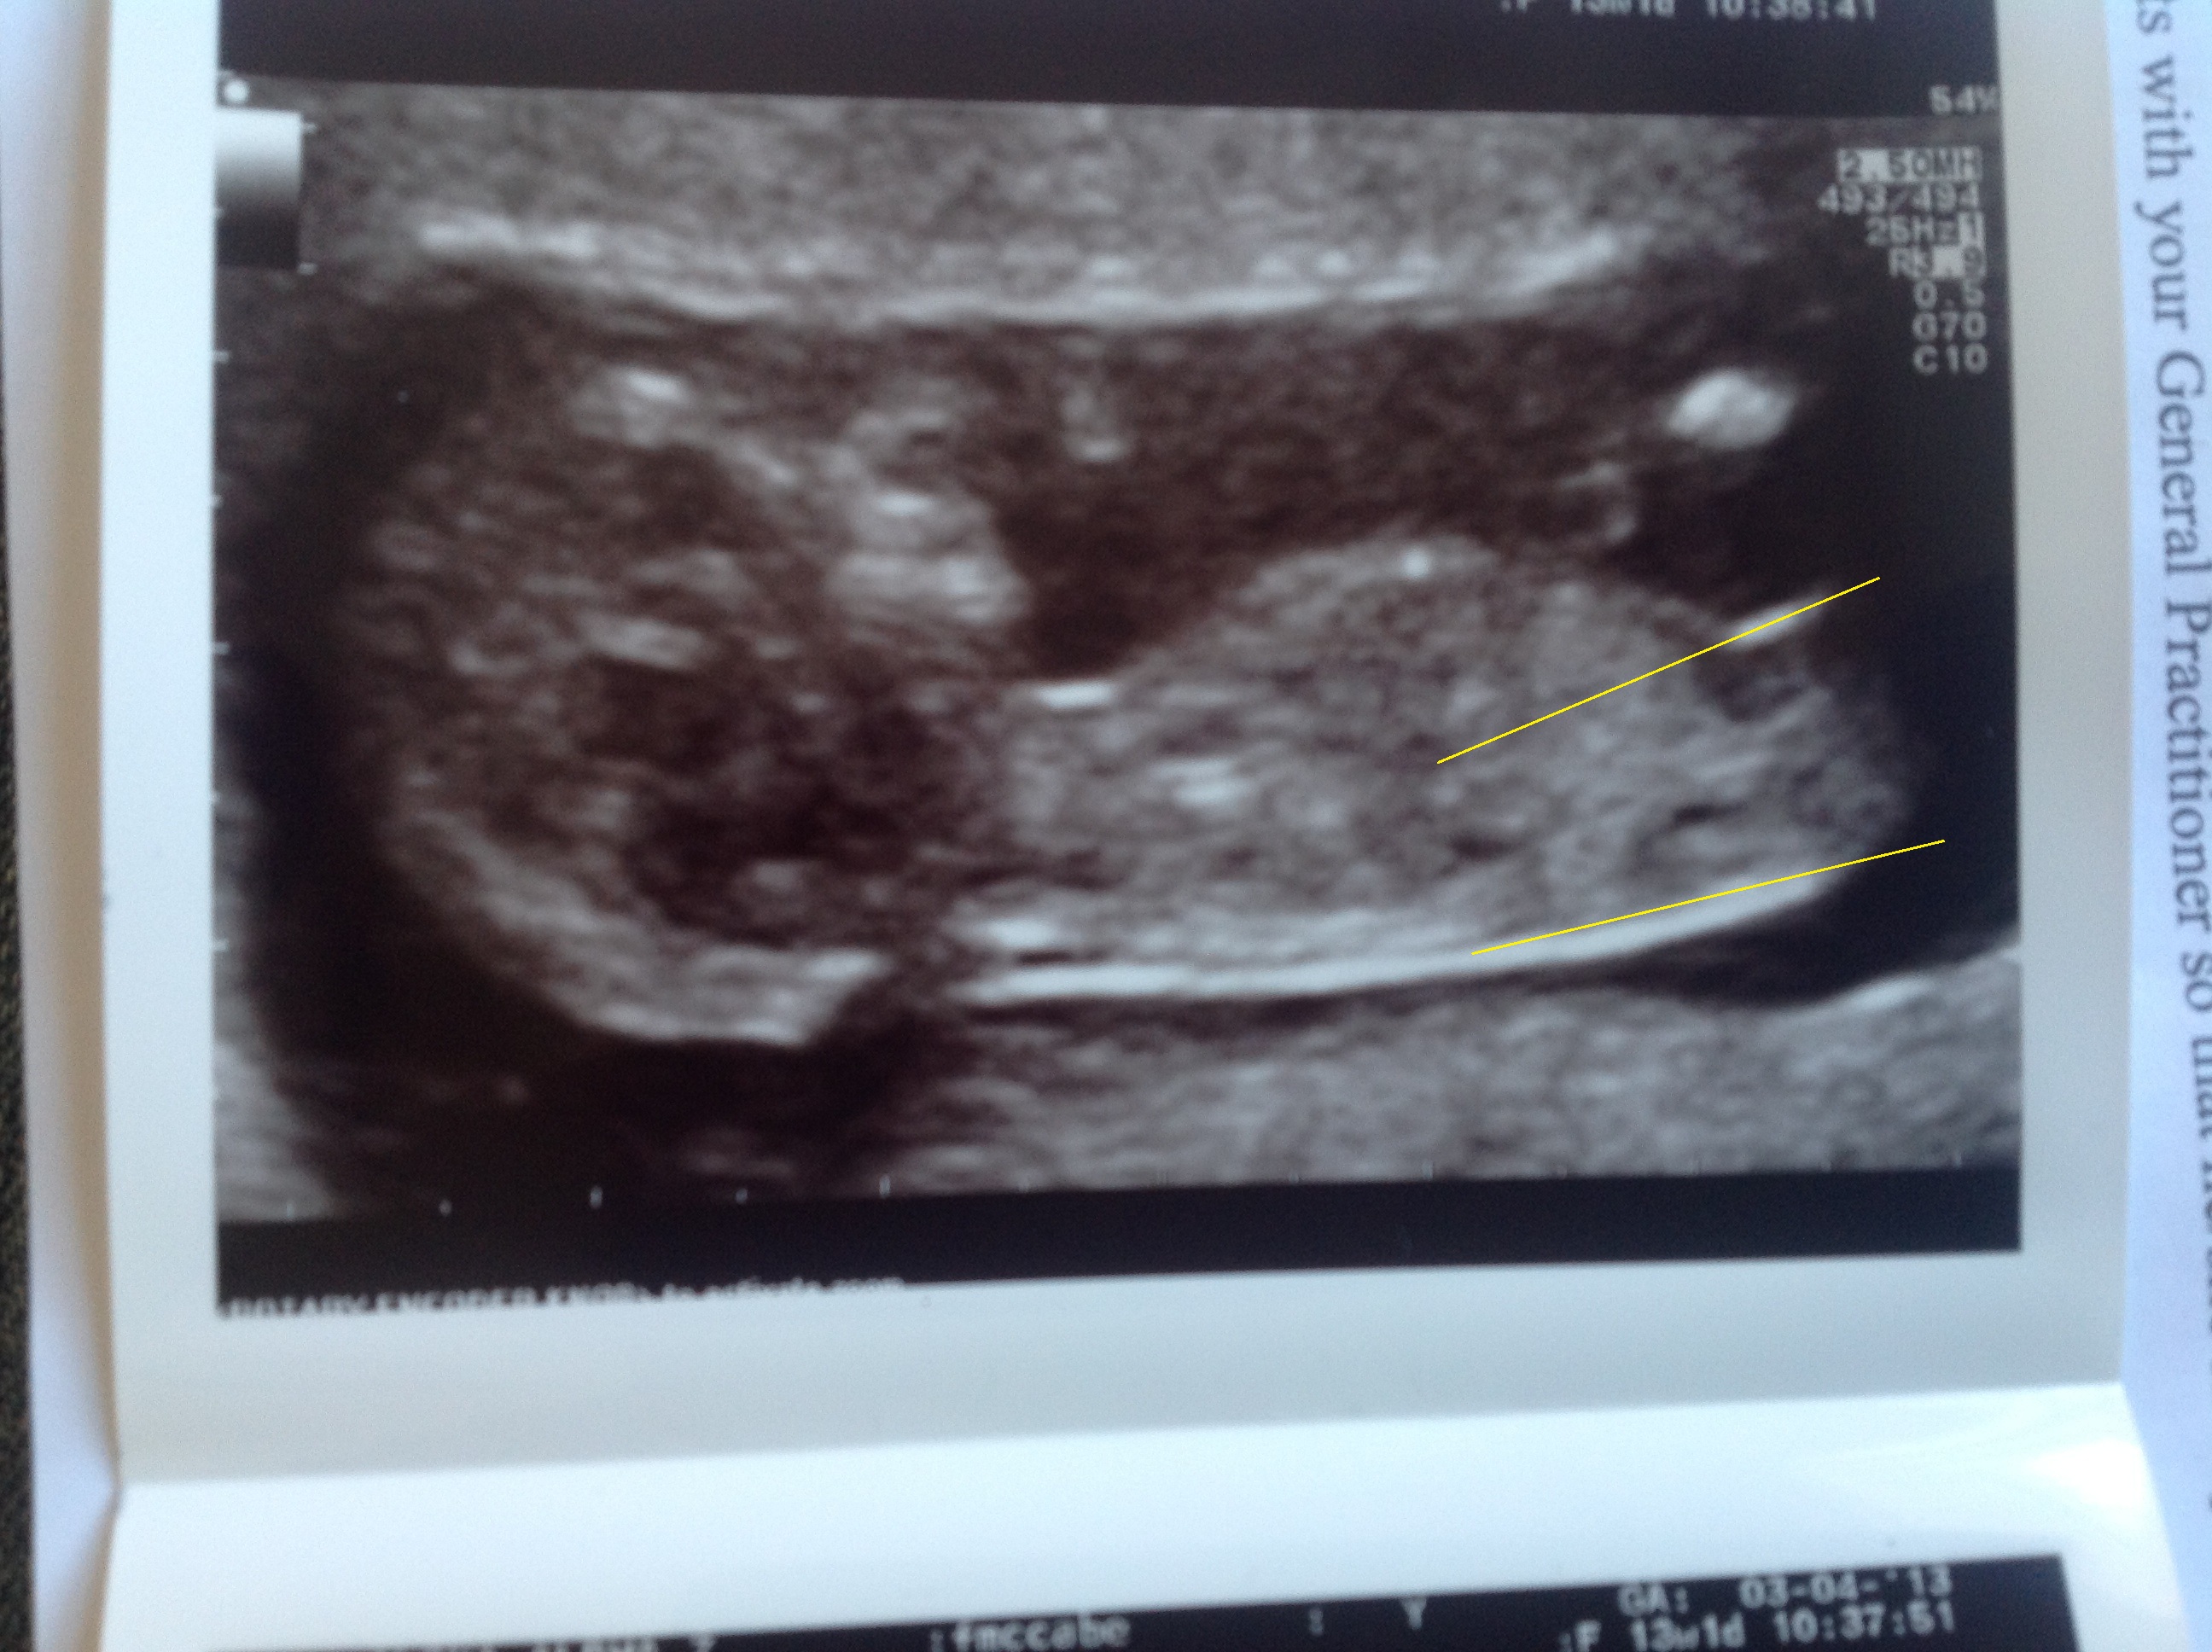

I drew on the lines, have I got it right?? And the lines are not parallel, are they?

Attachment 10304

Attachment 10307

They are not 30 degrees thats for sure! So hang on there :) I think u have a chance

YOUR picture...the bum looks ever so slightly tilted away from the camera which I think skews the angle towards up. The baby isn't in the ideal position as they were according to the study....otherwise were not counted in the results. The spine on your baby is very flat but the lines on the end (as well as the nub) seem to all tilt slightly up maybe due to this bum turning a bit.